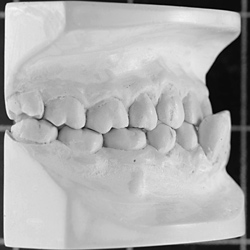

Kieferorthopädisch-kieferchirurgische Kombinationsbehandlungen

Wenn nicht nur die Zähne, sondern auch der Oberkiefer oder der Unterkiefer verändert werden müssen, so kann dies mit Spangen nur während der Wachstumsphasen gemacht werden.

Ist das Wachstum beendet, so kann diese Kieferveränderung nur operativ korrigiert werden.

Der Kieferorthopäde verschiebt die Zähne, der Kieferchirurg operiert den Kiefer. Anschließend sorgt der Kieferorthopäde wieder dafür, dass alles zusammenpasst.